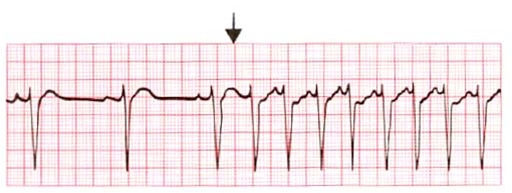

P-tak forud for QRS-komplekserne, oftest med kortere PQ-interval end ved normal sinusrytme, og P-takken ændrer konfiguration (udseende).

QRS-komplekserne bevarer i reglen deres form (normal QRS-bredde, <120 ms).